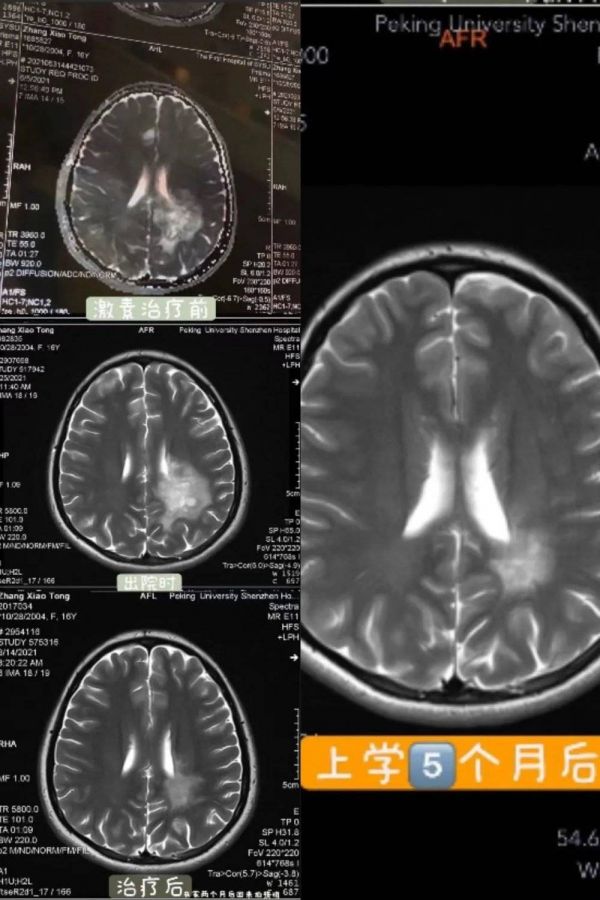

2021年5月,高二快结束的时候,有一天我突然发现自己写的字变得奇怪,还忘记了一些字该怎么写,紧接着的两三天,我身体的右半边失去知觉。紧急入院,我被诊断为疑似胶质瘤,医生把我爸爸拉到一边小声说可能情况不太好。于是,我就自己上网搜索,发现可能只剩几年的存活时间。来医院前,我预感到可能是因为压力导致的疾病,但怎么能是肿瘤呢?

想着即使要做开颅手术,也得去更好的医院,于是我们换到更权威的医院去。医生一看我,就说:“怪病啊,再照个核磁吧。”这次的结果,不是胶质瘤,而是与之很容易混淆的免疫系统疾病“脱髓鞘假瘤”。对我来说,这又是一个陌生的名词,不过,总比恶性肿瘤要好。

住院一个月,我做了激素冲击治疗。大量的激素使我掉发、长胖、胃消化功能变差,高三一整年我都戴着口罩。直到现在,我仍然担心病症复发,小心翼翼地维护着我的健康。

图 | 治疗过后的核磁图变化